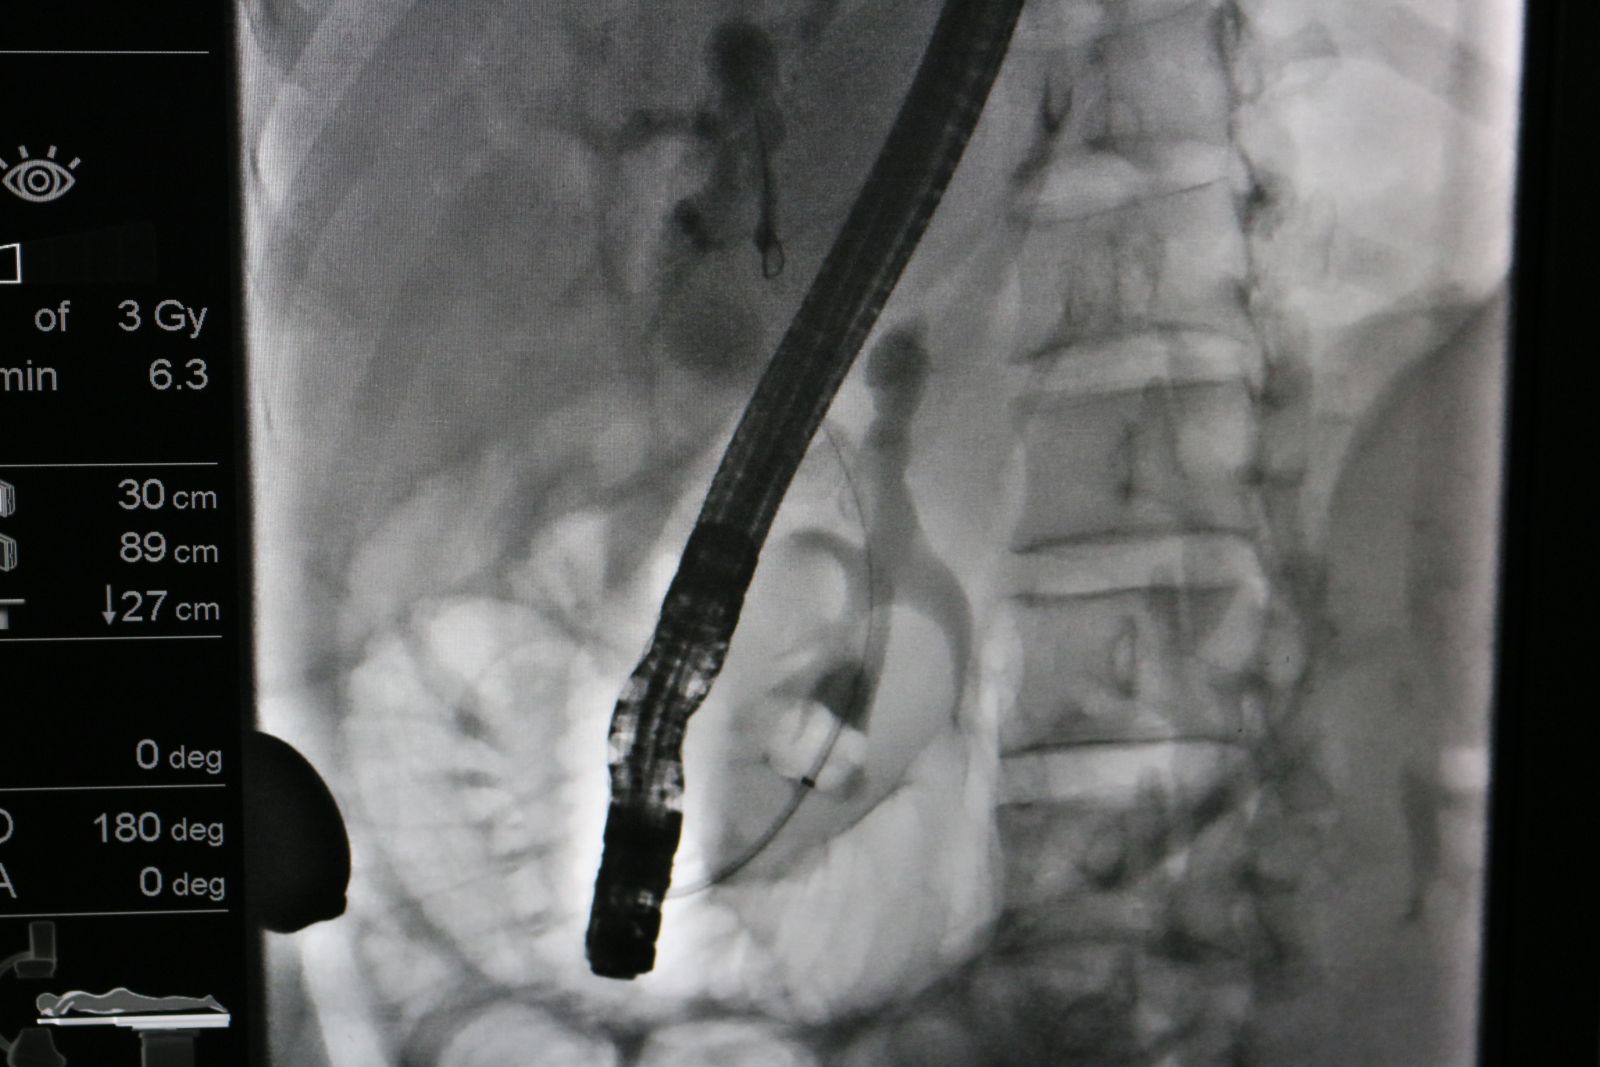

Ngày 04/01/2023, bệnh viện Đa khoa tỉnh Bắc Giang lần đầu tiên thực hiện thành công kỹ thuật nội soi mật tuỵ ngược dòng lấy sỏi ống mật chủ dưới sự chuyển giao kỹ thuật từ bệnh viện TWQĐ 108.

Bệnh nhân P.T.T (31 tuổi, địa chỉ ở Tân An,Yên Dũng, Bắc Giang) vào viện trong tình trạng sốt nhẹ, đau tức vùng hạ sườn phải, da vàng nhẹ, môi khô lưỡi bẩn. Người bệnh đến khám tại Bệnh viện Đa khoa tỉnh và nhập viện vào khoa Ngoại tiêu hoá điều trị. Qua khai thác tiền sử được biết, chị T đã phẫu thuật cắt túi mật từ tháng 2 năm 2022 và tiếp tục phẫu thuật lấy sỏi ống mật chủ cách đây 5 tháng. Ngay khi tiếp nhận người bệnh, các bác sĩ khoa Ngoại tổng hợp đã tiến hành thăm khám lâm sàng và cận lâm sàng. Kết quả xét nghiệm máu, siêu âm, chụp cắt lớp vi tính ổ bụng cho thấy người bệnh có sỏi ống mật chủ, đường kính 9x15mm, giãn đường mật trong và ngoài gan, nồng độ Bilirubin toàn phần và Bilirubin trực tiếp tăng cao.

Các bác sĩ của Bệnh viện Đa khoa tỉnh đã hội chẩn với các chuyên gia đầu ngành về tiêu hoá của Bệnh viện TWQĐ 108 và thống nhất chẩn đoán người bệnh tắc mật do sỏi ống mật chủ. Bệnh nhân được chỉ định nội soi mật tụy ngược dòng (ERCP) cấp cứu để can thiệp lấy sỏi ống mật chủ.

Ekip phẫu thuật do Bs.CKI Hà Huy Hùng, Phó trưởng khoa Thăm dò chức năng, bệnh viện Đa khoa tỉnh Bắc Giang cùng các cộng sự thực hiện; dưới sự tham gia giúp đỡ của TS.BS Dương Minh Thắng, PT Chủ nhiệm khoa Cấp cứu tiêu hoá A3-C, TS.BS Nguyễn Lâm Tùng, Phó Chủ nhiệm khoa Cấp cứu tiêu hoá A3-C, Bệnh viện TWQĐ 108.

Sau 45 phút đồng hồ, ca can thiệp đã diễn ra thuận lợi và an toàn, sỏi mật có kích thước 9x15mm được lấy hết ra khỏi ống mật chủ của người bệnh. Hiện tại, người bệnh ổn định, giảm đau bụng, tình trạng ứ mật được giải phóng và tiếp tục được theo dõi tại khoa Ngoại tiêu hoá.